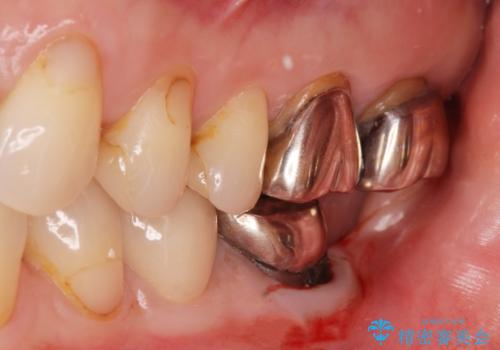

銀歯のやりかえ。

- 銀歯のやりかえ希望の患者様です。

患者様と話し合った結果、中の土台は外さず、被せ物のみのやりかえとなりました。

- ジルコニアクラウン・仮歯 12.1万円費用は治療当時の料金となります